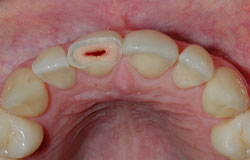

Los traumatismos dentales hacen referencia a lesiones en los dientes o tejidos blandos de la cavidad bucal, como labios, carrillos (parte interior de la mejilla) o lengua, originados por un impacto externo de forma imprevista. La severidad del trauma varía según la causa, pero los dientes más afectados tienden a ser los incisivos centrales y los laterales superiores.

Según la Asociación Internacional de Trauma Dental hay 15 tipos de traumatismos que van desde la concusión o golpe, fisuras del esmalte, desplazamientos laterales o frontales del diente, con movilidad o sangrado en tejido de encías circundantes; hasta fracturas del diente o que involucran pérdida de la pulpa, fracturas de la raíz, intrusiones (pieza incrustada en encía), avulsión (pérdida completa del diente) y fracturas alveolares y de la mandíbula.